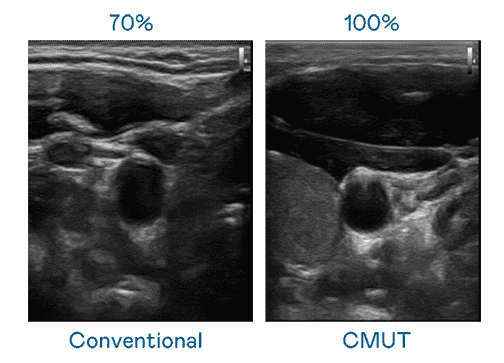

CMUT 技术是一种用电容式微机电元件来产生超音波讯号的技术。。与传统 PZT 压电式技术相比,,,,CMUT 频宽增加 30%,,更宽频的超音波讯号让影像解析度大幅提升,,,是实现高影像品质医疗超音波扫描、、、促进精准医疗发展的关键技术。。

大频宽带来超清晰影像

超音波影像的解析度高低,,,首先取决于探头能发出的讯号频宽。。z6mg·人生就是博 CMUT 可提供高清晰的超音波讯号,,,,提供高频宽、、、高灵敏度、、、影像纹理细节更高的超音波影像,,,,协助医护人员缩短影像判读时间及利用精准的医疗影像进行诊断。。。。